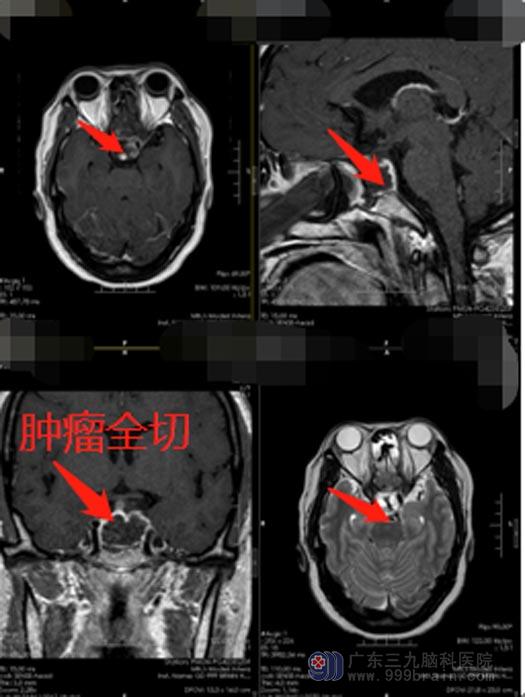

征得雷女士及家属同意,手术准备就绪后,由鲁明主刀在全麻下行“内镜经鼻蝶鞍区垂体瘤切除术+颅底重建术”。运用神经内镜借鼻腔通道,经蝶窦微创直达垂体切除肿瘤,具有肿瘤暴露佳,创伤和危险性小,手术时间缩短、颅面外观无损伤等优点,可很大程度降低对脑组织、脑神经和血管的损伤,微创切除垂体瘤,确保患者安全。

顺利将鞍内肿物切除后,雷女士视物模糊、头痛、恶心等症状明显缓解,目前恢复良好,已康复出院。